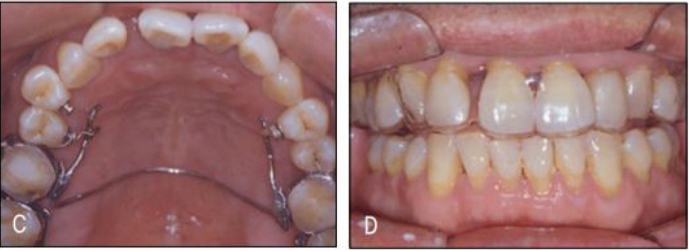

[증례] 치주질환으로 심한 병적 치아이동(pathologic tooth migration, PTM)이 나타나 기능적, 심미적 회복을 위해 교정을 한 65세 고령 환자 증례. 전악 치근단사진에서 볼 수 있듯이 전치 뿐 아니라 구치부 전 치아에 걸쳐 심한 염증이 발생하고 이로 인해 구치부에서도 PTM 이 심하게 나타나 치주치료 후 구치 교합이 불안한 상태가 초래 된 환자이었다.

치주치료 후 보철의사에게 돌아온 환자의 교합을 보고 dual bite 상태에서는 보철을 할 수 없는 바, 치주질환 이전의 교합 상태로의 교정을 의뢰하였다. 전체적으로 치주지지가 불량하여 움직일 치아만 제대로 움직 이는 치료가 매우 어려운 케이스이기 때문에 기공비용이 다소 많이 들지만 간단하게 치료 할 수 있는 투명교정장치를 사용하여 치료하기로 하였다. 구치부의 경우 협측전위된 우측 제1, 제2소구치와 좌측 제1소 구치 이동을 위해 투명교정장치를 사용할 경우 다수의 장치가 필요할 것으로 생각되어 대구치를 고정원으로 하여 소구치를 간단 하게 이동시키는 TPA 장치를 이용하였으며, 이후 투명교정장치로 전치부 공간을 클로져하여 간단하게 교정을 마무리 하였다(그 림 23-5, 6).